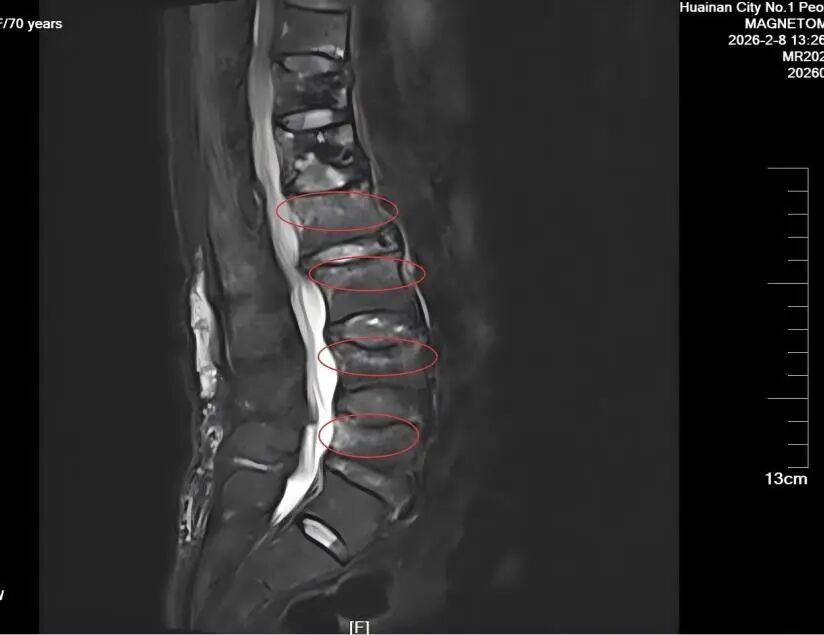

然而,骨质疏松带来的脆弱骨骼,让方奶奶的生活依然需要小心翼翼。今年2月,一次不经意的转身,熟悉的剧痛再次袭来。检查结果显示,她的腰椎又出现了新的“塌方”——L2到L5四个节段发生了压缩性骨折。

面对高龄、多病、多节段骨折的复杂情况,是选择保守治疗忍受长期卧床的痛苦,还是再次手术?我院骨科团队再次迎难而上。经过全面评估,决定为方奶奶实施“腰椎椎体后凸成形术”,一次性解决多个椎体的问题,手术非常成功!

根据骨折风险的高低,治疗策略也有所不同。骨质疏松的老年骨折患者建议进行核磁共振检查,获得更准确的诊断影像。